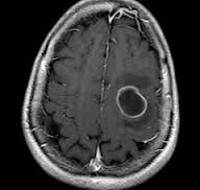

Точность диагностирования абсцесса головного мозга с помощью КТ головного мозга зависит от стадии формирования абсцесса. На ранних стадиях заболевания диагностика затруднена. На этапе раннего энцефалита (1-3 сутки) КТ определяет зону сниженной плотности неправильной формы. Введенное контрастное вещество накапливается неравномерно, преимущественно периферических отделах очага, реже в центре. На более поздних этапах энцефалита контуры очага приобретают ровные округлые очертания. Контрастное вещество распределяется равномерно, по всей периферии очага; плотность центральной зоны очага при этом не меняется. Однако на повторной КТ (через 30-40 минут) определяется диффузия контраста в центр капсулы, а также наличие его и в периферической зоне, что не характерно для злокачественных новообразований.

Инкапсулированный абсцесс мозга на КТ имеет вид округлого объемного образования с четкими ровными контурами повышенной плотности (фиброзная капсула). В центре капсулы зона пониженной плотности (гной), по периферии видна зона отека. Введенное контрастное вещество накапливается в виде кольца (по контуру фиброзной капсулы) с небольшой прилежащей зоной глиоза. На повторной КТ (через 30-40 минут) контрастное вещество не определяется.

МРТ головного мозга — более точный метод диагностирования абсцесса головного мозга. При проведении МРТ на первых стадиях формирования абсцесса мозга (1-9 сутки) энцефалитический очаг выглядит: на Т1-взвешенных изображениях — гипоинтенсивным, на Т2-взвешенных изображениях — гиперинтенсивным. МРТ на поздней (капсулированной) стадии абсцесса головного мозга: на Т1-взвешенных изображениях абсцесс выглядит, как зона пониженного сигнала в центре и на периферии (в зоне отека), а по контуру капсулы сигнал гиперинтенсивный. На Т2-взвешенных изображениях центр абсцесса изо- или гипоинтенсивный, в периферической зоне (зоне отека) гиперинтенсивный. Контур капсулы четко очерчен.